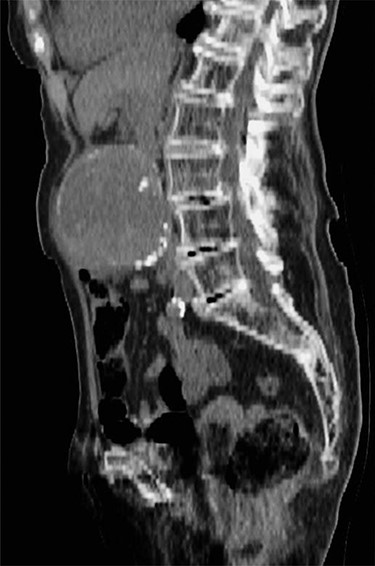

A 100-year-old woman presented to the emergency department with a 4-day history of central abdominal pain. On examination, she was found to have a pulsatile, expansile aneurysm with stable observations. Computed tomography (CT) aortogram demonstrated an infrarenal AAA of 8 cm (Fig. 1). A detailed discussion took place with the patient and her family, explaining the high likelihood of mortality without surgery and the operative risks involved. The patient had a background of atrial fibrillation, hypertension, mild dementia and a recent hip replacement. She was able to walk for one mile and carry out most activities of daily living independently. Under these circumstances, we felt it appropriate to proceed, taking into consideration good preoperative functional status, limited comorbidities, anatomical suitability for EVAR under local anaesthetic and good recovery following a recent hemiarthroplasty. The patient underwent EVAR successfully, followed by an uneventful postoperative recovery. No endoleak or complication of the graft was noted at follow-up and the patient survived for 2 years following intervention.